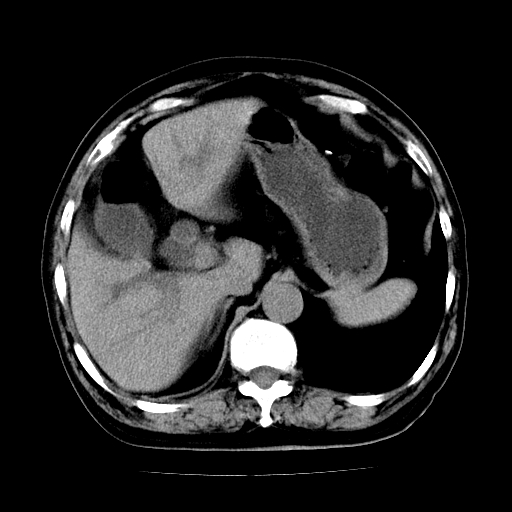

标题: CT25226:男,71岁,皮肤黄染四天。 [打印本页]

男,71岁,皮肤黄染四天。

肝内外胆管及胆总管上段扩张,考虑为梗阻所致,建议mrcp检查。

肝内胆管,胆囊,肝总管级部分胆总扩大张

考虑胆总管癌并肝内外胆管扩张。

胰腺上端胆总管内见软组织影,强化不明显,结合临床,还是考虑低位梗阻性黄疸,胆总管癌可能性大